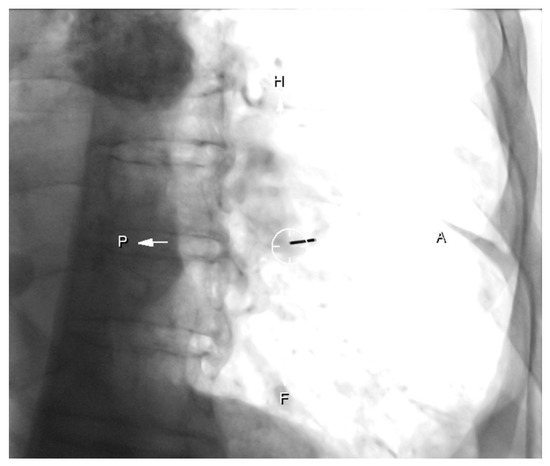

Cone-Beam CT-Guided Lung Biopsies: Results in 94 Patients

- Cone-Beam CT-guided biopsy is a highly accurate and safe technique with a sensitivity of 91.5% and a specificity of 100%.

- Risk factors for pneumothorax are a deeper location of the nodule and prone position of the patient in the procedure.